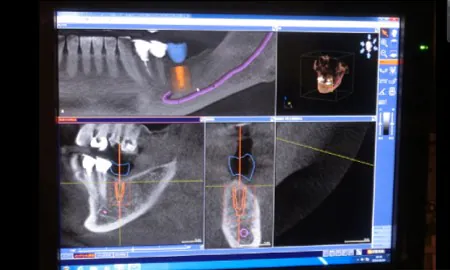

当院では、歯科用CTを使用して顎の骨の厚みや密度などを確認し、インプラント体を埋め込む位置を決めます。

当院では、歯科用CTを使用して顎の骨の厚みや密度などを確認し、インプラント体を埋め込む位置を決めます。

さらに、サージカルガイドを作成し、インプラント体を適切な位置・深さ・角度で埋め込めるようにしております。3Dシミュレーションを行い、患者さんの治療に対する納得感を高めることも重視しています。

さらに、3S systemというCT撮影とインプラントの精密な設計、歯科技工士による正確な補綴物の作製、歯科医師による的確なオペレーションにより、治療の安全性と満足度の両方の向上に努めております。